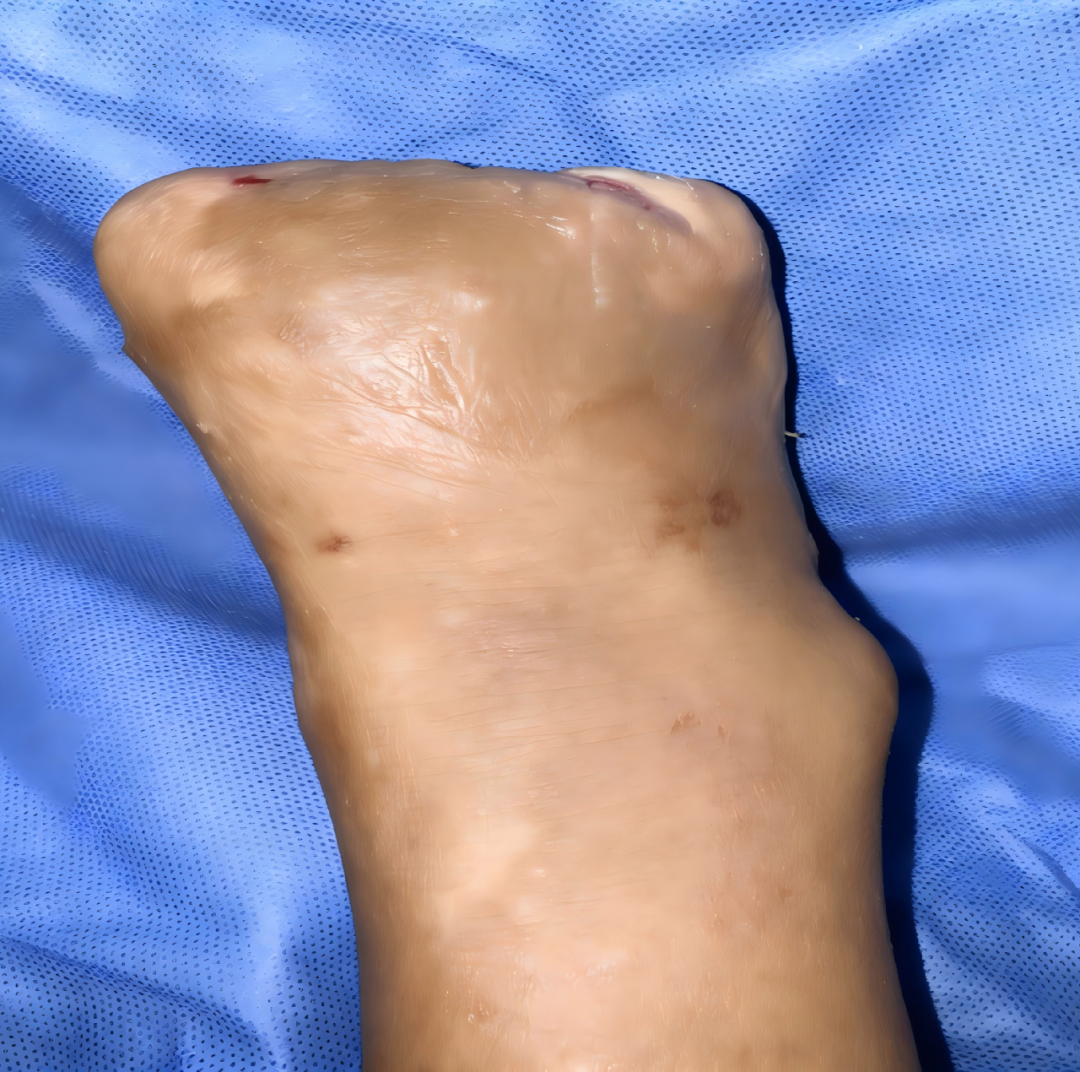

针对其重度感染及组织缺损状况,我院创面修复与烧伤科团队制定阶梯式精准手术方案,分阶段施治:首次手术重点清除坏死足趾及骨髓炎病灶,彻底控制感染,同时预置皮瓣,为后续修复奠定基础;待创面条件改善后,团队开展二次联合手术,采用带蒂轴型皮瓣移植联合筋膜组织瓣成形技术,结合负压封闭引流,有效修复足底组织缺损,破解局部血运差、修复难度大的难题。术后,团队持续关注皮瓣血运与创面愈合情况,及时开展再次清创与负压治疗,凭借成熟的围术期管理与应急处置能力,最终实现创面基本愈合,患者病情显著好转,现已康复出院。

术后两个月